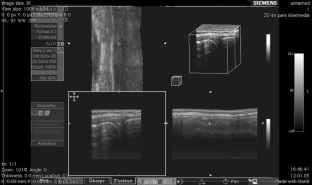

Abb. 1